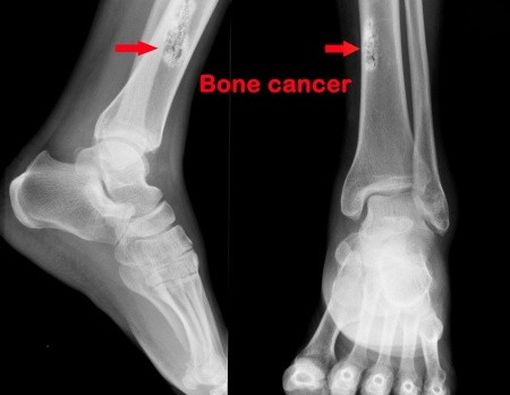

Bagaimana mendiagnosis kanker tulang?

Dokter akan melakukan wawancara medis mendetil dan pemeriksaan fisik menyeluruh, selain itu akan dilakukan juga pemeriksaan penunjang seperti bone scan, CT-scan, MRI, X-ray, ataubiopsi. Setelah diagnosis ditegakkan, barulah dokter akan menentukan stadium kanker. (Baca: 10 Cara Menghindari Kanker)